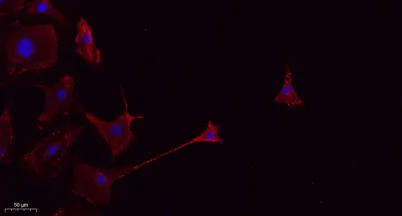

- Validated Applications: WB, IHC, IF, ELISA

- Dilution: Western Blot: 1/500 - 1/2000. IHC-p: 1:100-300 ELISA: 1/20000. IF 1:100-300 Not yet tested in other applications.